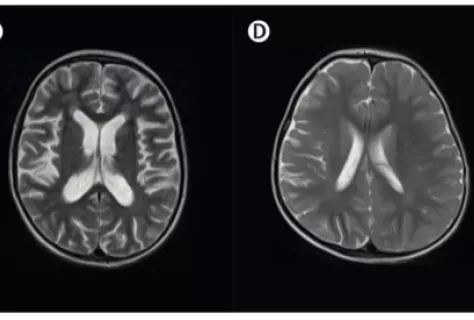

Beta hemoglobinopathies, such as sickle cell anemia and beta thalassemia, are severe genetic diseases caused by defects in hemoglobin, the molecule that carries oxygen in the blood. These defects lead to chronic anemia and can cause serious damage to various organs. One “natural” way of compensating for this defect is the continued expression of fetal hemoglobin (HbF), a form normally present in the fetus and capable of making up for the faulty adult hemoglobin. Researchers at Institut Imagine are exploring innovative strategies for reactivating this HbF in patients. One is based on the genetic editing of blood stem cells, a promising approach which, however, still needs to be perfected in terms of safety. In parallel, the “Chromatin and gene regulation during development” team, headed by Annarita Miccio, is developing an epigenetic approach, which acts not on the DNA code, but on its regulators: chemical marks that control the activation or silencing of genes. By precisely modifying these marks, HbF expression can be revived without affecting the DNA itself. Simone Amistadi and Letizia Fontana's work, published in Nucleic Acid Research, shows that this method could offer a safe and effective alternative for treating these rare diseases, while enriching our understanding of the mechanisms that regulate gene expression.